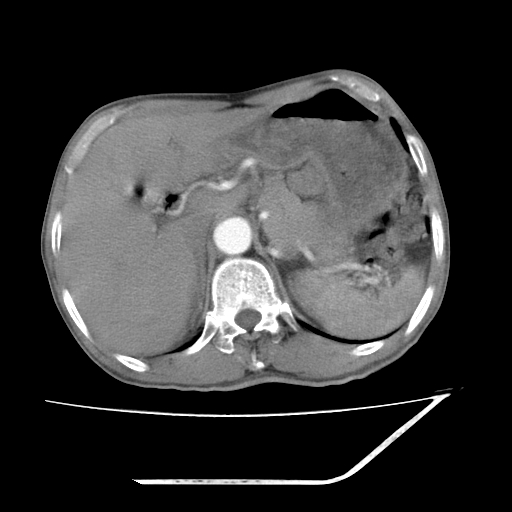

增强

考虑右肾盂癌,肾动脉受侵,右肾功能减退,右肾盂输尿管积水,管壁增厚,考虑种植转移,应该把下面扫完的

支持右侧肾盂癌伴肾静脉瘤栓形成可能性大,右肾结石.肝右叶后段低密度影,不除外转移.

右肾盂旁ca并肾静脉瘤栓形成/肾功能降低。

右肾结石。

右肾盂癌,肾动脉受侵,右肾盂输尿管积水,管壁增厚,考虑种植转移

右肾盂移行细胞癌并右输尿管中段转移.肾积水.

支持 右侧肾盂癌伴肾静脉瘤栓形成可能性大,右肾结石;肝右叶后段低密度影,不除外转移。

1.右侧肾盂癌伴肾盂积水。

2.肾脏功能减退,原因有:(1)肾动脉受侵。(2)肾静脉受侵(3)肾积水,等。本例,肾动脉显影较好,但受压明显;肾静脉无明显显示,受压或静脉癌栓,下腔静脉腔内未见明显充盈缺损。

3.右侧上段输尿管扩张,原因:(1)积水所致;(2)种植。